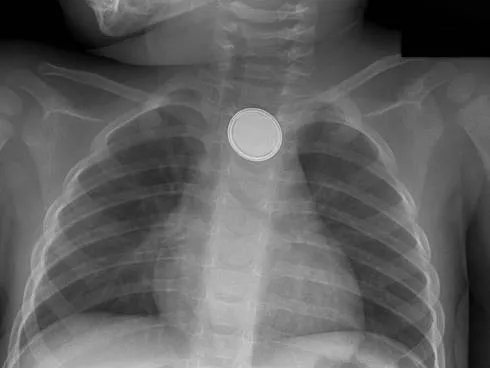

- X-ray (AP/Lat): First-line. Shows radio-opaque FBs.

- 📌 Coin Sign: Esophagus (AP: O, Lat: |), Trachea (AP: |, Lat: O).

⭐ A coin in the esophagus typically appears as a circle (en face) on an AP X-ray, while in the trachea it appears as a circle on a lateral X-ray (sagittal orientation).

- Esophageal coins: Appear circular on AP X-ray. Tracheal coins are edge-on.